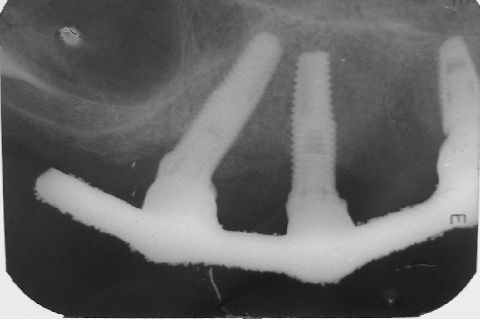

Atualização do caso clínico que já postei, "REABILITAÇÃO EM MAXILA ATRÓFICA COM IMPLANTES", um caso que inclui expansão do rebordo estreito com cinzel e martelo, expansores rosqueáveis, enxerto e instalação dos implantes distais inclinados tangenciando seio maxilar. Inclui esvaziamento do forame nasopalatino e preenchimento com biomaterial para instalação de dois implantes próximos dele. Cirurgia realizada em única sessão, com instalação dos 6 implantes. Para os colegas que não conheceram e/ou esqueceram da apresentação, este é o resumo do caso na fase cirúrgica.http://www.youtube.com/watch?v=BtvexFexRPA&hd=1

FASE PROTÉTICA DA REABILITAÇÃO EM MAXILA ATRÓFICA...incluindo a reabertura, instalação dos minipilares e PTR provisória reembasada sobre os cilindros de proteção.